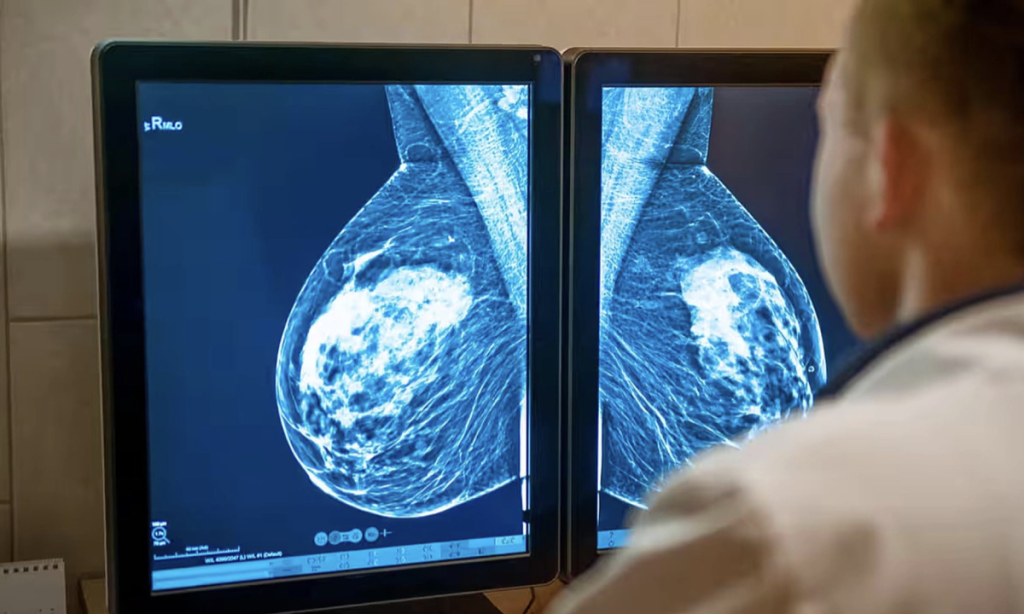

Ung thư vú nếu phát hiện ở giai đoạn sớm, quá trình điều trị thường rất nhẹ nhàng, chi phí thấp và phần lớn được bảo hiểm y tế chi trả. Ảnh: Alamy

Ung thư vú nếu phát hiện ở giai đoạn sớm, quá trình điều trị thường rất nhẹ nhàng, chi phí thấp và phần lớn được bảo hiểm y tế chi trả. Tuy nhiên, với những trường hợp phát hiện muộn hoặc thuộc các thể bệnh khó như tam âm và HER2 dương tính, chi phí có thể leo thang từ hàng trăm triệu đến hàng tỷ đồng cho các loại thuốc nhắm trúng đích và miễn dịch.